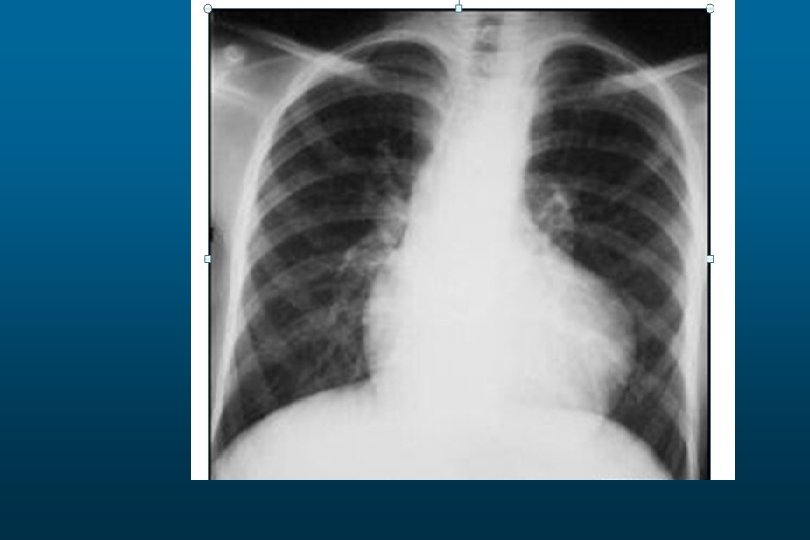

Left Lower Lobe Pneumonia